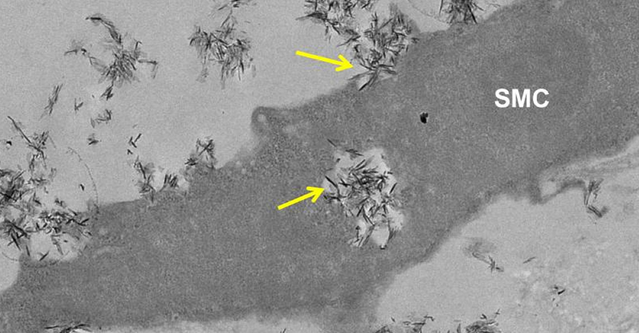

研究人員已經(jīng)發(fā)現(xiàn)我們血液中的蛋白如何降低隨著年齡增長的血管損傷,以及諸如動脈粥樣硬化和關節(jié)炎的條件。 鈣化是心臟發(fā)作和中風的主要危險因素。磷酸鈣(CAP )的晶體可導致血管硬化,它們通常發(fā)現(xiàn)于骨骼和牙齒中,隨著年齡增長在軟組織中建立或作為疾病的一個結果。這可能會導致動脈粥樣硬化患者的并發(fā)癥,這是英國的一個死亡主要原因,它會導致動脈變厚,并且有被阻塞的危險。 在由英國心臟基金會資助的研究中,研究人員發(fā)現(xiàn),微小的CAP晶體被血管細胞所吸收,從而導致異常高濃度的鈣離子,這已被證明是有毒的。他們發(fā)現(xiàn),血液中的兩種蛋白質,胎球蛋白-A和白蛋白,可減緩血管細胞對CAP晶體的吸收,從而降低鈣離子的釋放和防止損傷。 “一個細胞內的鈣水平的微小變化可調控正常細胞的許多方面的功能。然而,當鈣含量變得過多時,這個細胞就會死亡。而胎球蛋白-A和白蛋白通過延緩這些晶體的吸收和降低鈣離子的釋放,可以幫助鈣離子保持在一個安全水平。” 這項研究可為開發(fā)預防和減少磷酸鈣晶體的破壞作用的治療提供線索。 |